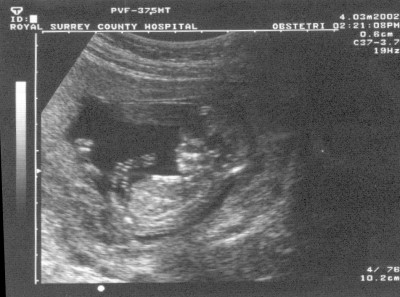

For you see, when the sound of your greeting reached my

ears, the baby leaped for joy inside me!….no wait on the news they tell me it is just a fetus.

Since the legalization of abortion in 1973, there have been approximately 50 million abortions performed in the United States.